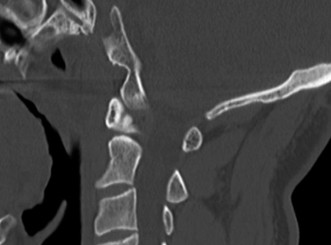

Recognize surgical and nonsurgical indications for a thoracic lymphoma? Definitively manage a thoracic lymphoma? CASE 13 A 23-year-old man was involved in a high-speed motor vehicle accident. On presentation to the trauma bay, his chief complaint was neck pain. Physical examination demonstrated that he was neurologically intact. Images of the cervical spine are shown in Figure 1–19A–B. Full workup demonstrated no other injuries.

Figure 1–19 A–B

The correct answer is (B). The imaging clearly demonstrates a Hangman’s fracture, also known as a C2 traumatic spondylolisthesis. The hallmark of this injury is a fracture through the pars interarticularis of C2, which effectively dissociates the anterior elements from the posterior arch and facet joints. A Jefferson fracture refers to C1 ring fractures that can have varying degrees of lateral displacement. There is no evidence of vertebral body comminution with posterior vertebral body involvement, which would be characteristic of a burst fracture. While some Hangman’s fractures can be associated with facet dislocation, there is no evidence of this on the imaging.

The correct answer is (B). Type I fractures have minimal horizontal displacement, no angulation, and the C2–3 disc remains intact. Type II fractures are both displaced and angulated, presumably hinging around the anterior longitudinal ligament. Importantly, these fractures reduce with longitudinal traction. Type IIA fractures have minimal horizontal displacement but are significantly angulated. It is presumed that the anterior fragment rotates in place, most likely disrupting the anterior longitudinal ligament. These injuries are worsened by traction and reduced with axial compression. Type III fractures have bilateral C2–3 facet dislocations.

The correct answer is (B). While type I fractures can be treated immediately in a hard collar, type II fractures are best treated initially with traction to achieve fracture reduction. After a short period of traction, the patient should be placed in a halo vest to allow mobilization. As indicated above, type IIA fractures should not be placed in traction; patients should be placed in a halo vest with some axial compression applied. Type III fractures require surgical reduction of the facet dislocation and internal stabilization. Objectives: Did you learn...? Identify a Hangman’s fracture based on imaging? Understand the classification of Hangman’s fractures?